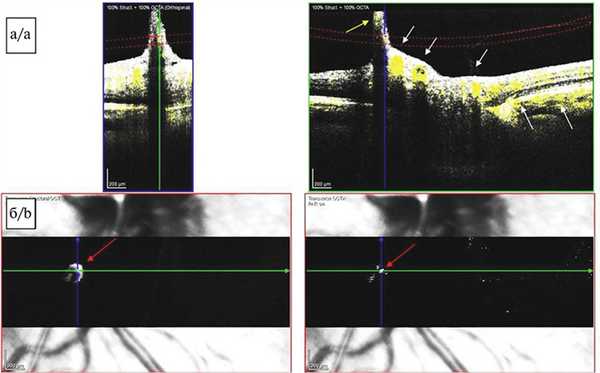

На поперечных срезах изображения перипапиллярной области, полученных методом ОКТА (SPECTRALIS HRA+OCT с модулем ОКТ-ангиографии, Heidelberg Engineering, Германия), отчетливо визуализировался кровоток от ретинальных и хориоидальных сосудов, а также отмечен сигнал средней рефлективности от тяжа (КК) соответственно локализации ПГА в заднем отделе стекловидного тела (рис. 4, а). Можно было бы предположить, что имеет место артефакт изображения, но присутствие кровотока подтверждалось наличием гиперрефлективного локуса в той же проекции на en-face снимках (рис. 4, б). В области сосочка Бергмейстера активный кровоток не определялся. Кроме того, проведение исследования позволило выявить наличие задней тракционной отслойки СТ и элевацию ретинального контура в зоне сосочка Бергмейстера.

Рис. 4. Картина оптической когерентной томографии-ангиографии.

а — томограмма диска зрительного нерва, поперечный срез, сегментация на уровне заднего отдела стекловидного тела. Визуализируется сигнал кровотока от ретинальных и хориоидальных сосудов (белые стрелки), а также слабый сигнал кровотока от персистирующей гиалоидной артерии (желтая стрелка). В области сосочка Бергмейстера активный кровоток не выявлен; б — томограмма диска зрительного нерва, изображение en-face, проекция нижненазального сектора перипапиллярной области. Визуализируется гиперрефлективный участок, соответствующий сигналу кровотока в сосуде гиалоидного канала (красные стрелки).